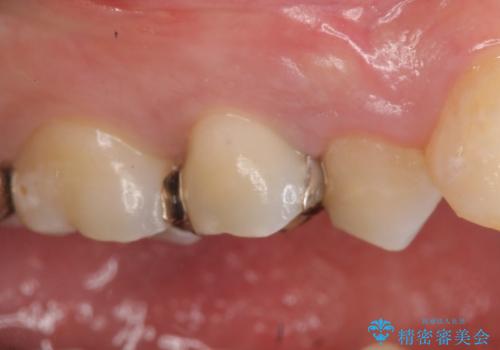

セラミックインレー しみる歯の治療